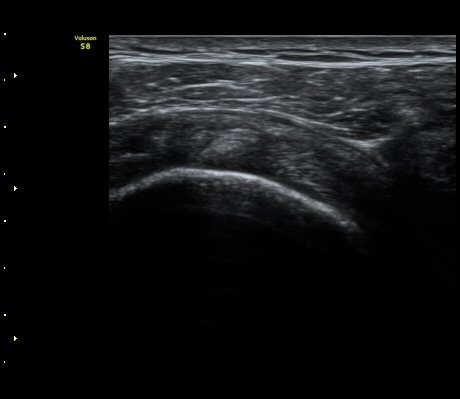

3°³¿ù ÈÄ ÃßÀû°Ë»ç

2049205267_d4912430_US181205109.jpg